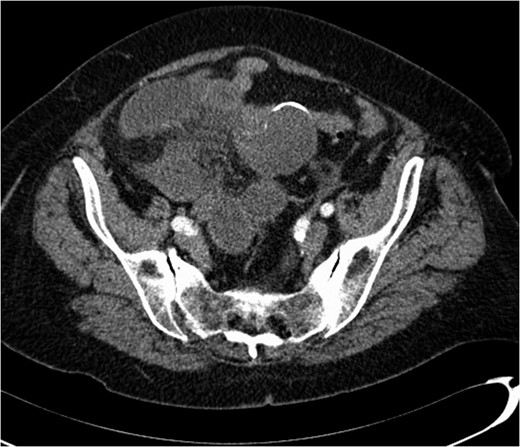

A 74-year-old female, with a background history of hypertension and hypothyroidism, presented to the emergency department with a 6-h history of sudden onset generalized abdominal pain. The pain was colicky in nature, associated with nausea and refractory to analgesia. Examination revealed tenderness in the right upper quadrant and epigastrium. Blood tests were normal except for a mild neutrophilia (7.5 × 109/l) and lactate of 2.5 mmol/l. A computed tomography (CT) scan of her abdomen and pelvis was performed which showed abnormal loops of small bowel along the right side of the abdomen with mesenteric fat stranding. A partially calcified structure was noted lying medial to the loops of bowel (Figs 1 and 2). The patient proceeded to have an explorative laparotomy performed. Intraoperative findings revealed an ischaemic loop of small bowel wrapped around a mass in the mesentery adjacent to the sigmoid colon (Fig. 3). The patient underwent a partial small bowel resection with primary anastomosis and en-bloc resection of the mass with the formation of an end colostomy. The final histological revealed a 6 × 4 × 4 cm cystic colonic duplication cyst separate but adjacent to the sigmoid colon. The inner lining of the cyst revealed mucinous epithelium, with mucin contained within. The wall of the cyst was sclerotic with occasional lymphoid aggregates, smooth muscle and neurovascular bundles (Fig. 4). The patient made a good recovery and was discharged home.

Axial CT scan showing a partially calcified structure adjacent to loops of small bowel.